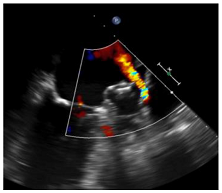

| TEE | CT | |

|---|---|---|

| DEFINITION/METHODS |

|

![]() | ![]() | |

| LIMITATIONS |

| INCIDENCE * | PDL: 26% [24] | LAA Patency: 55% [24] PDL: 57% [24] |